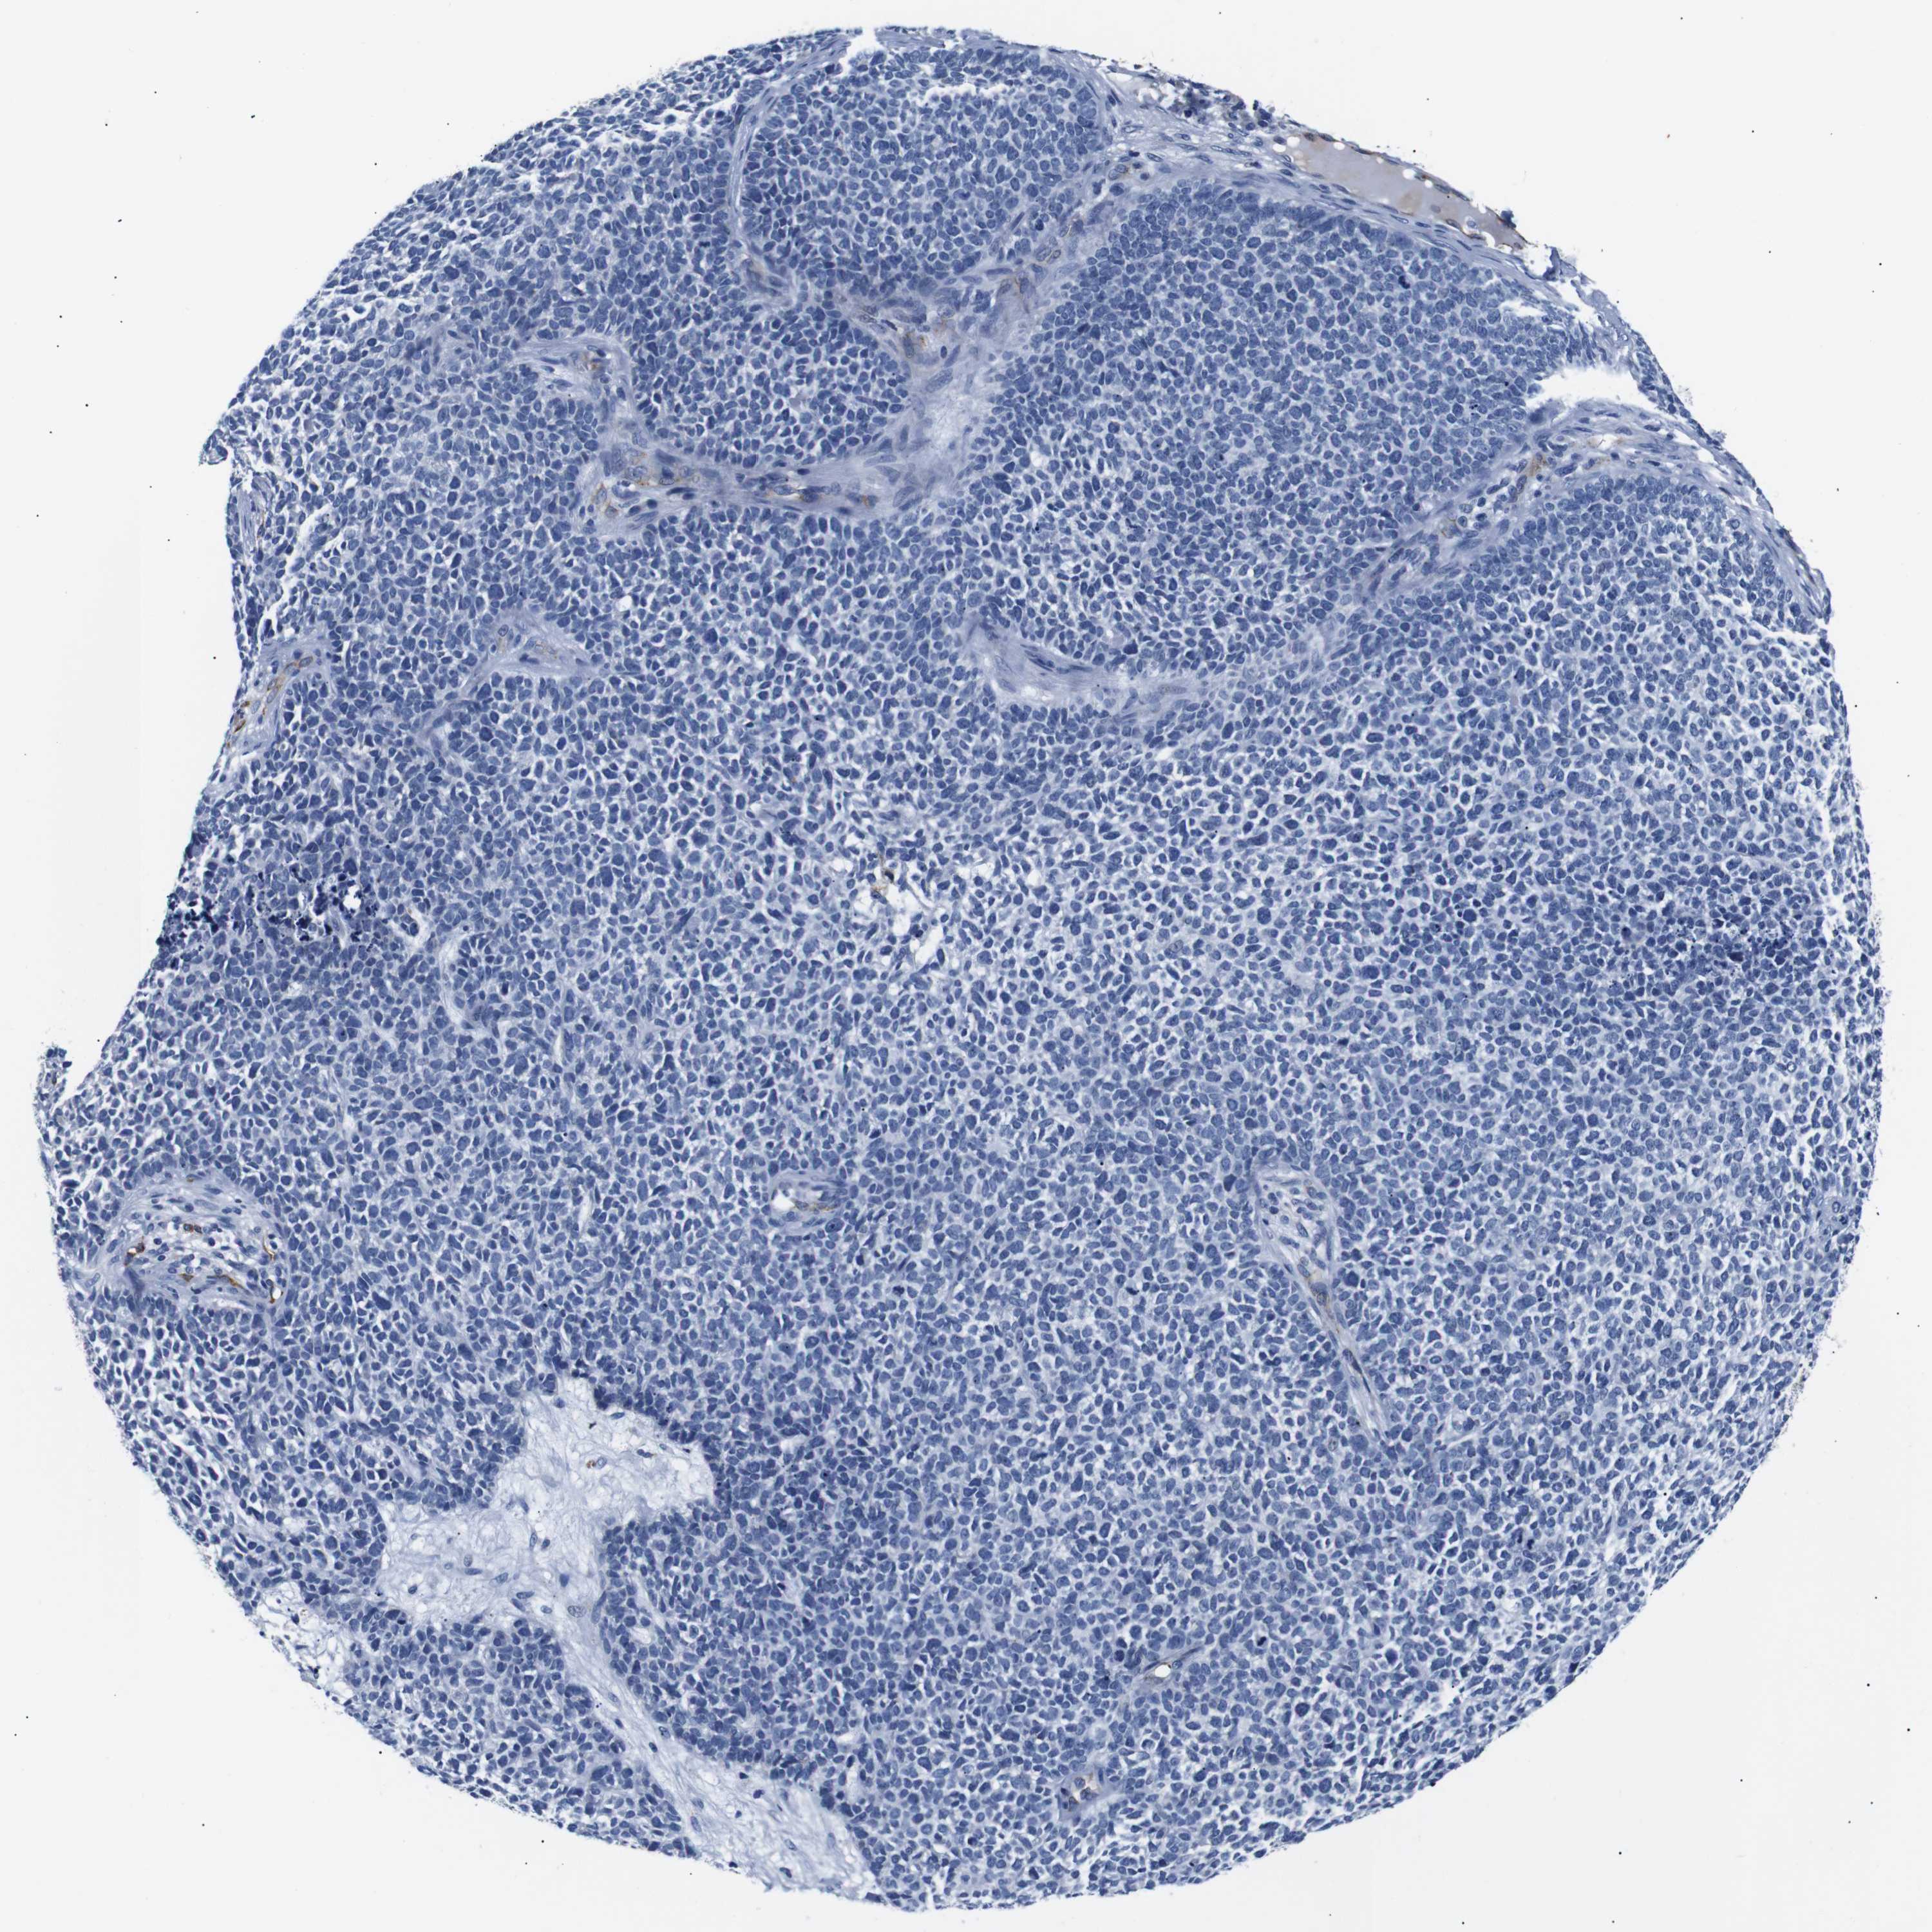

SKIN CANCER - Protein expressioni

A mouse-over function shows sample information and annotation data. Click on an image to view it in a full screen mode. Samples can be filtered based on level of antibody staining by selecting one or several of the following categories: high, medium, low and not detected. The assay and annotation is described here.

Antibody stainingi

Antibody staining in the annotated cell types in the current human tissue is reported as not detected, low, medium, or high, based on conventional immunohistochemistry profiling in selected tissues. This score is based on the combination of the staining intensity and fraction of stained cells.

Each image is clickable and will lead to virtual microscopy that enables deeper exploration of all samples and also displays staining intensity scores, fraction scores and subcellular localization as well as patient and tissue information for each sample.

Antibody HPA005895

Antibody CAB013536

Squamous cell carcinoma, NOS

Basal cell carcinoma